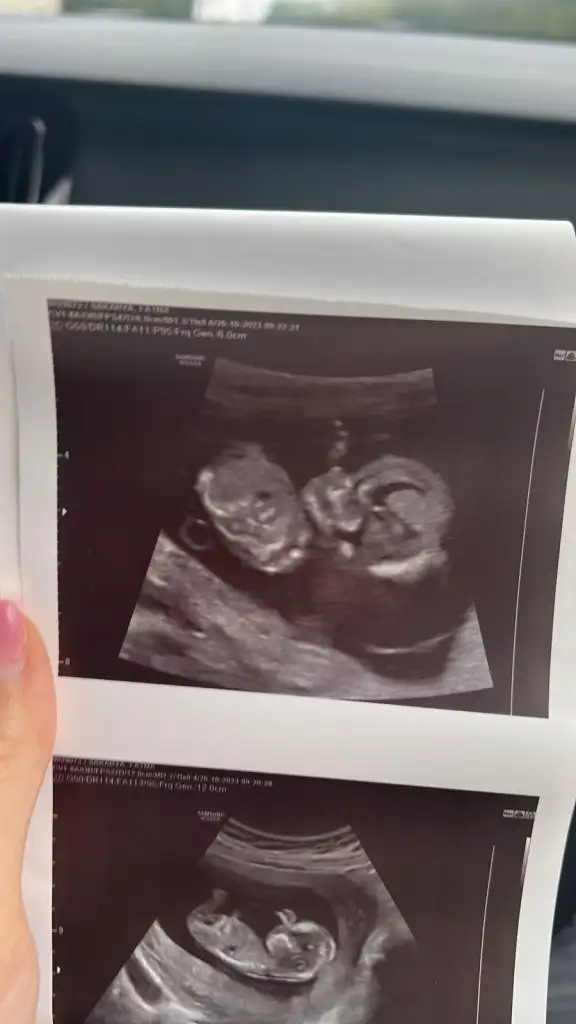

12 haftalik bakarmisiniz cinsiyete?

Eklentiler

• IMG-20231026-WA0002.webp

31,3 KB · Görüntüleme: 44

• IMG-20231026-WA0001.webp

18,8 KB · Görüntüleme: 49

• IMG-20231026-WA0000.webp

15,9 KB · Görüntüleme: 46